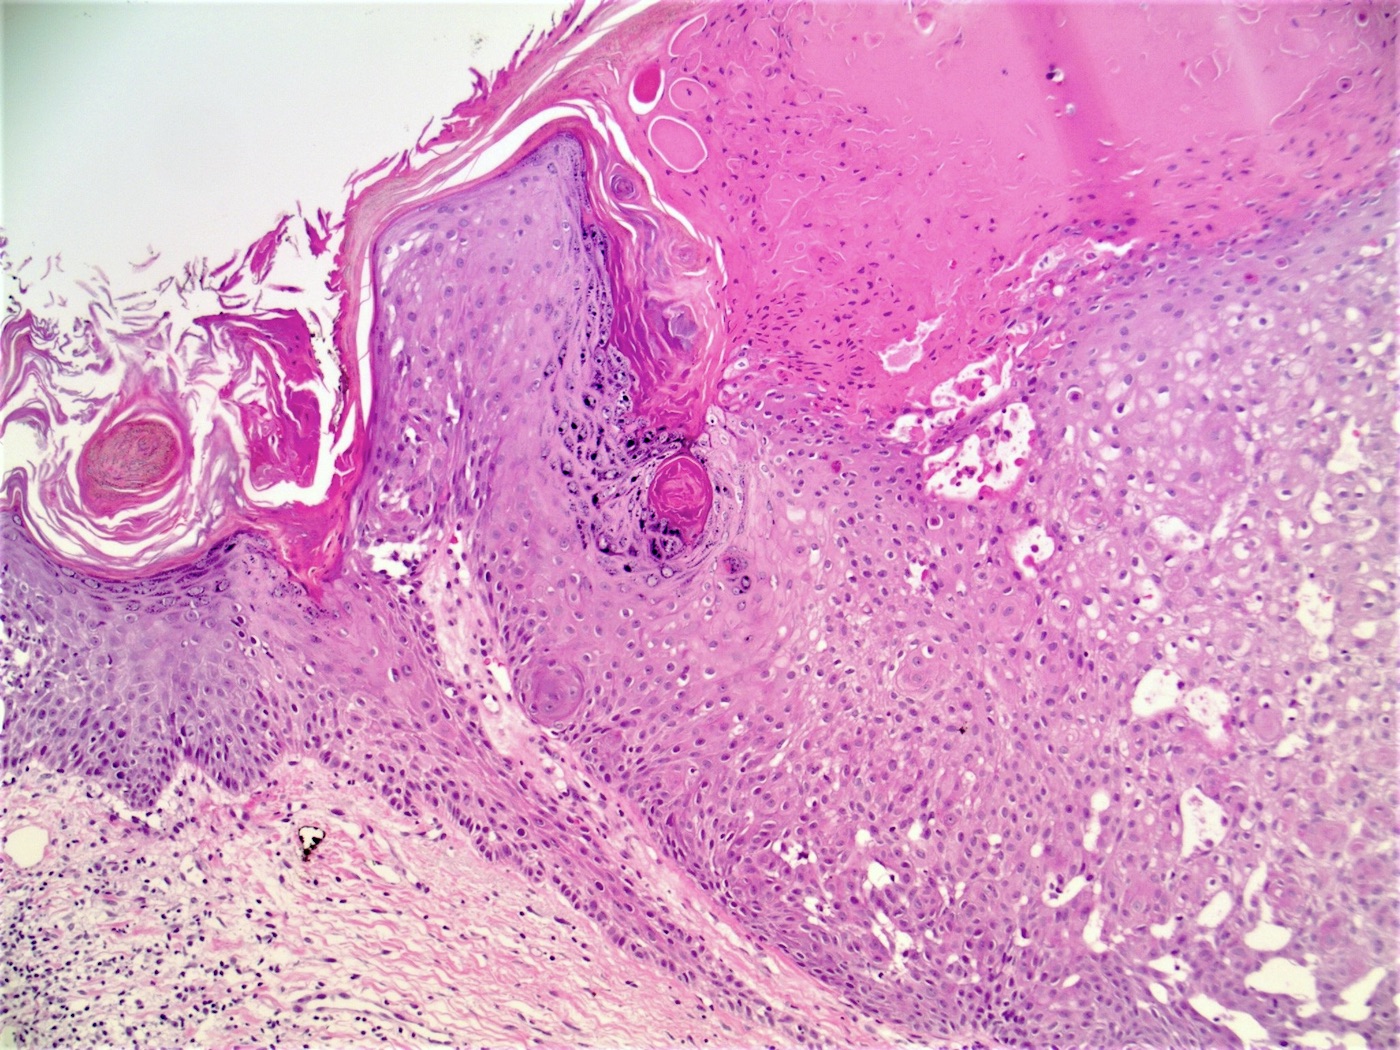

Microscopic (histologic) description

- Well circumscribed, endophytic tumor with large lobules or finger-like extensions that resemble expanded follicles

- Variable number of squamous eddies

- Occasional mitoses within peripheral basaloid cells

- Histologic variants have been described (J Cutan Pathol 1984;11:387):

- Papillomatous wart-like: exophytic with overlying hyperkeratosis and parakeratosis

- Keratoacanthoma-like: central exoendophytic mass

- Cystic type: irregular clefts within tumor and formation of small cysts